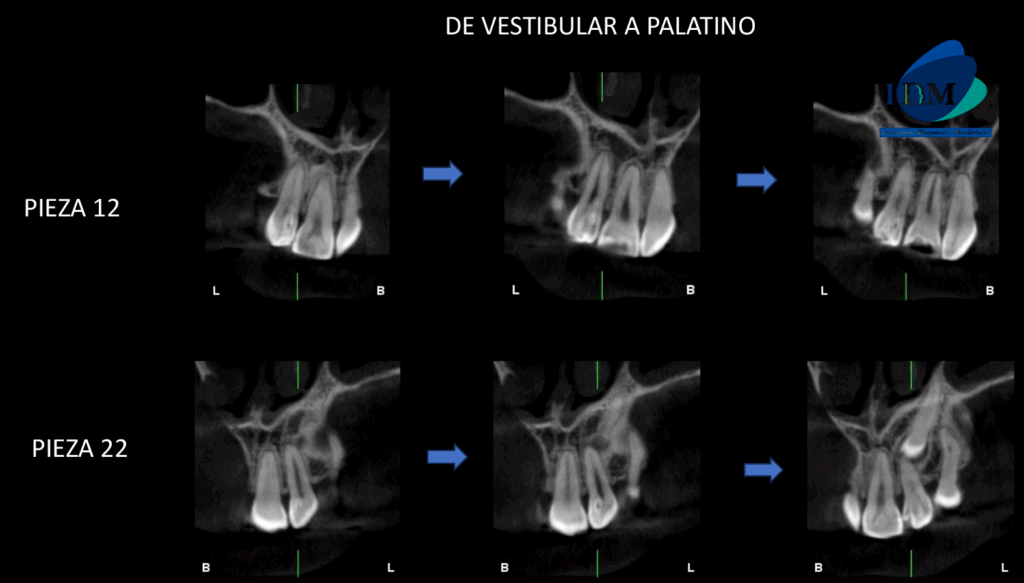

A la evaluación de la tomografía de campo mediano en cortes axiales, transaxiales y tangenciales se evidencia un detalle que en la panorámica paso un poco inadvertida y es que las piezas 12 y 22 presentan una alteración de la morfología coronaria compatible con dientes invaginados.

CORTES TANGENCIALES